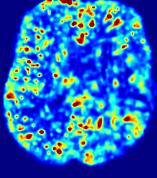

LesionRefer to captionRefer to captionRefer to captionRefer to captionRefer to captionRefer to caption𝐕rgbsubscript𝐕𝑟𝑔𝑏{\bf{V}}_{rgb}Refer to captionRefer to captionRefer to captionRefer to captionRefer to captionRefer to caption𝐕2subscriptnorm𝐕2{\|\bf{V}}\|_{2}Refer to captionRefer to captionRefer to captionRefer to captionRefer to captionRefer to captionRefer to caption3.53.53.52.82.82.82.12.12.11.41.41.40.70.70.70.00.00.0(mm/s)𝑚𝑚𝑠(mm/s)D𝐷DRefer to captionRefer to captionRefer to captionRefer to captionRefer to captionRefer to captionRefer to caption0.0200.0200.0200.0160.0160.0160.0120.0120.0120.0080.0080.0080.0040.0040.0040.0000.0000.000(mm2/s)𝑚superscript𝑚2𝑠(mm^{2}/s)Slice #1Slice #2Slice #3Slice #4Slice #5Slice #6

Figure 4: PIANO feature maps for another patient in the ISLES 2017 training set, where the lesion is located in the right hemisphere. Top row: segmented stroke lesion region (white) on different slices. The corresponding slices for the PIANO feature maps are shown in the following rows.

For a better insight into an estimated velocity field 𝐕𝐕{\bf{V}} and diffusion field 𝐃𝐃{\bf{D}}, we compute the following maps: (1) 𝐕rgbsubscript𝐕𝑟𝑔𝑏{\bf{V}}_{rgb}: Color-coded orientation map of 𝐕=(Vx,Vy,Vz)T𝐕superscriptsuperscript𝑉𝑥superscript𝑉𝑦superscript𝑉𝑧𝑇{\bf{V}}=(V^{x},V^{y},V^{z})^{T}, obtained by normalizing 𝐕𝐕{\bf{V}} to unit length and mapping its 3 components to red, green, blue respectively; (2) 𝐕2subscriptnorm𝐕2\|{\bf{V}}\|_{2}: 222 norm of 𝐕𝐕{\bf{V}}; (3) D𝐷D: scalar field in Eq. 5.

Fig. 3 and Fig. 4 show the PIANO feature maps estimated from two ISLES 2017 patients: all are highly consistent with the lesion in both cases. Details of the blood flow trajectories are revealed in 𝐕rgbsubscript𝐕𝑟𝑔𝑏{\bf{V}}_{rgb} by the ridged patterns and the sharp changes of colors in the unaffected (right) hemisphere, while the flat patterns appearing within the lesion provide little directional information about the velocity and indicate low velocity magnitudes. Velocity magnitudes are more directly visualized via 𝐕2subscriptnorm𝐕2\|{\bf{V}}\|_{2}, from which one can easily locate the lesion where 𝐕2subscriptnorm𝐕2\|{\bf{V}}\|_{2} is low. D𝐷D also indicates lower diffusion values in the lesion, though with less contrast potentially due to the fact that it captures the accumulated effect of CA diffusion at the voxel-level.